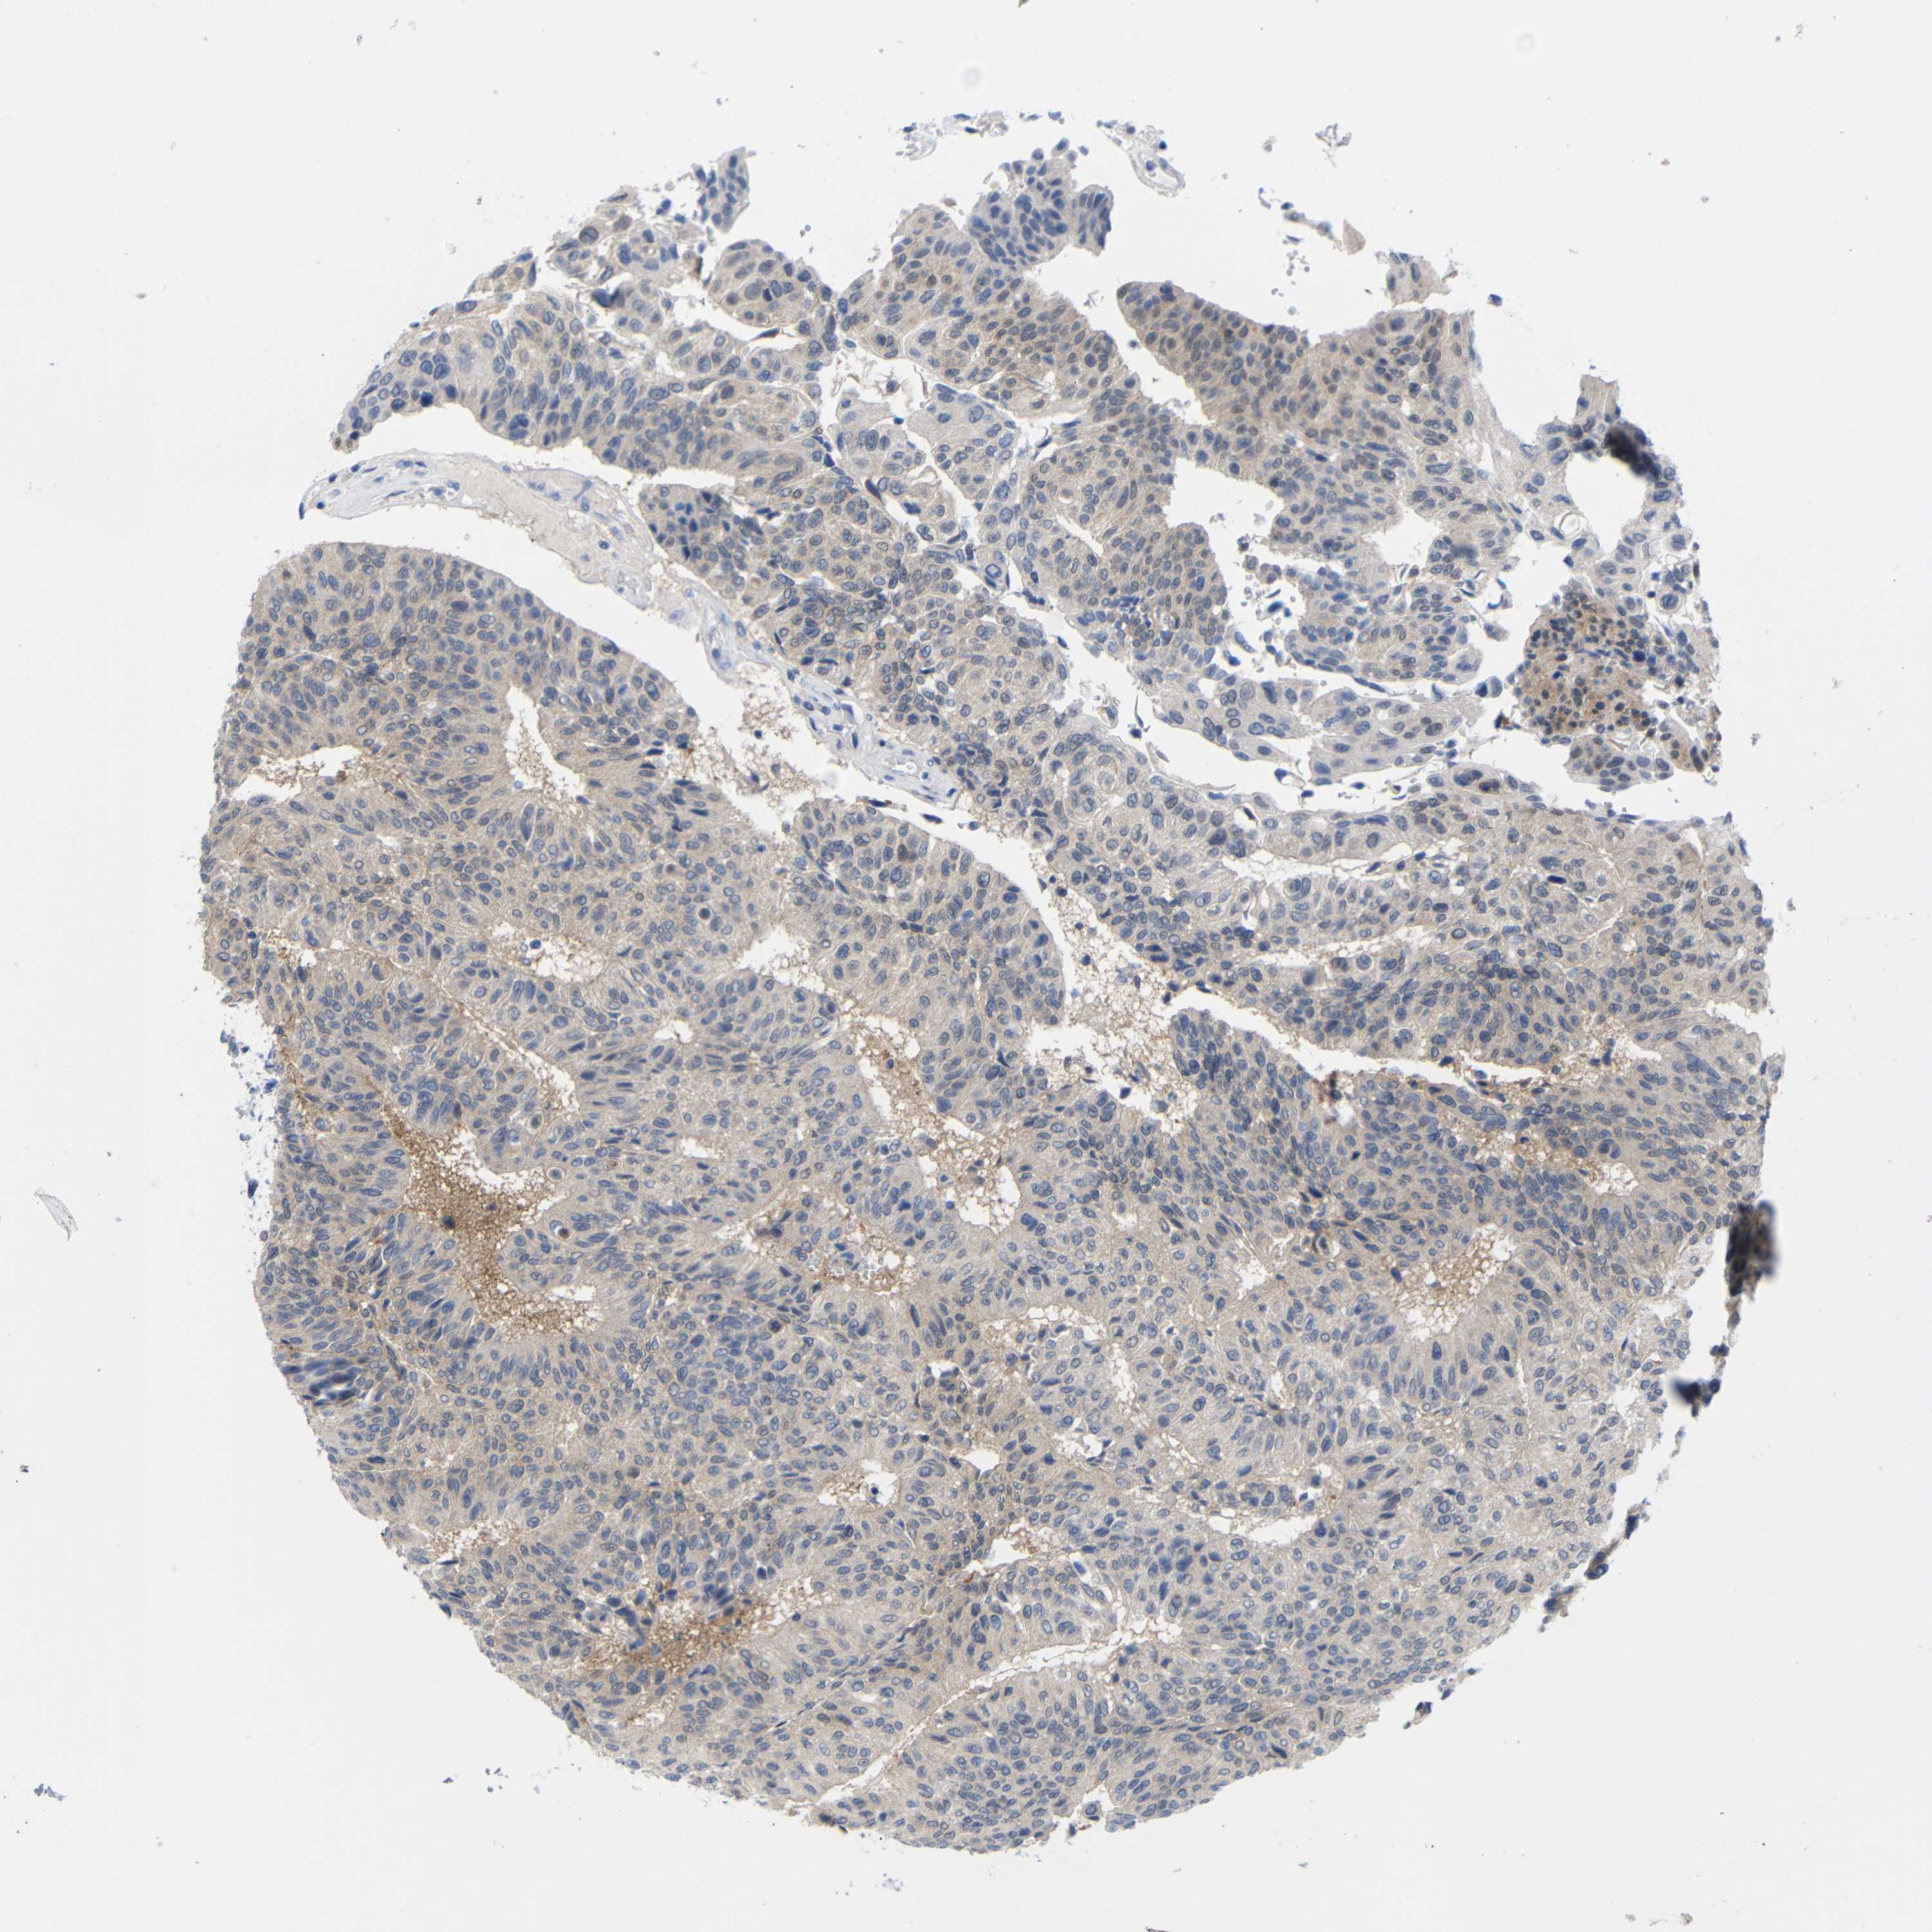

UROTHELIAL CANCER - Protein expressioni

A mouse-over function shows sample information and annotation data. Click on an image to view it in a full screen mode. Samples can be filtered based on level of antibody staining by selecting one or several of the following categories: high, medium, low and not detected. The assay and annotation is described here.

Note that samples used for immunohistochemistry by the Human Protein Atlas do not correspond to samples in the TCGA dataset.

Antibody stainingi

Antibody staining in the annotated cell types in the current human tissue is reported as not detected, low, medium, or high, based on conventional immunohistochemistry profiling in selected tissues. This score is based on the combination of the staining intensity and fraction of stained cells.

Each image is clickable and will lead to virtual microscopy that enables deeper exploration of all samples and also displays staining intensity scores, fraction scores and subcellular localization as well as patient and tissue information for each sample.

Antibody CAB080063

Urothelial carcinoma, NOS